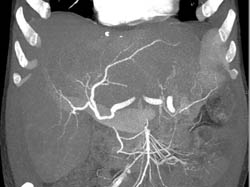

Lymphoma of the Liver